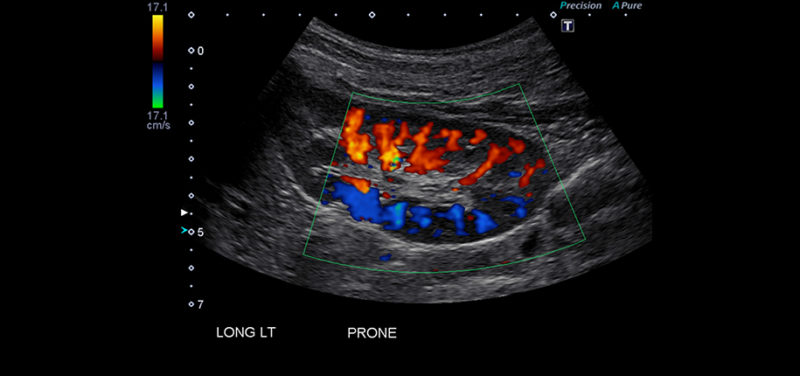

Renal and Ureteral Evaluation: The technologist systematically sweeps the transducer across the upper bilateral flanks to evaluate the kidneys.

The sonographer measures the exact total length, width, and cortical thickness of both organs. The renal pelvis is carefully examined for any signs of physical dilation caused by trapped infected fluid. The technologist will then attempt to trace the pathway of the ureters downward toward the pelvis.

When evaluating the retroperitoneal and pelvic cavities, the interpreting radiologist systematically analyzes the acoustic data to identify specific structural deviations. Normal, healthy urinary organs produce standard, predictable acoustic echoes.

However, when bacterial pathogens invade the tissues, the resulting inflammation, swelling, and fluid accumulation drastically alter these normal echo patterns.

Documenting these precise urinary tract infection ultrasound findings provides the referring physician with definitive evidence regarding the infection’s physical severity and precise anatomical location.

During the evaluation, the radiologist cross references the real time visual data against a standardized list of recognized clinical pathologies. The presence of any of the following structural abnormalities immediately confirms a complicated diagnosis.